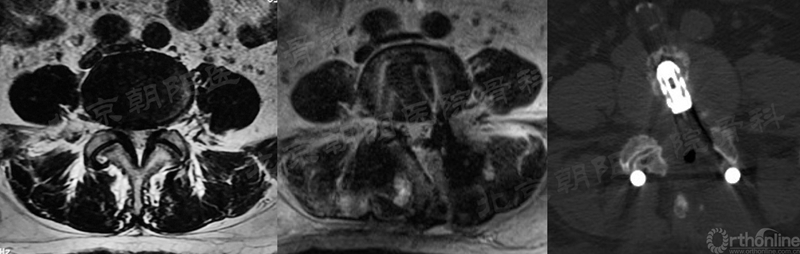

1、 镜下迷失——减压部位错误

#1例UBE,术前计划减压范围如绿色部分,术中减压操作集中在了硬膜背侧,甚至多数时候在对侧操作,实际减压部位在红色部分,使椎管减压的效果不理想。